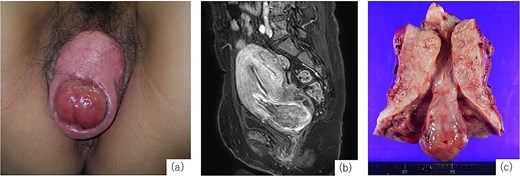

A 52-year-old woman, gravida 4, para 3, with regular menstrual cycles presented with a 9-year history of vaginal discomfort and recent abnormal menstrual bleeding. She had a history of mild POP, but no prior treatment. Although the discomfort had not improved, she did not visit a gynecologist. She visited a gynecologist with complaints of increased menstrual bleeding and a drooping sensation and was diagnosed with fibroid expulsion and POP, and 2 months later, referred to our department. The gynecological assessment revealed fibroid expulsion with complete uterine prolapse, cystocele, rectocele and a prolapsed mass visible in the external cervical os (Fig. 1a). Contrast-enhanced magnetic resonance imaging (MRI) identified a pedunculated submucosal fibroid (69 × 42 × 50 mm) originating from the anterior uterine wall and extending through the cervical canal (Fig. 1b). Her blood tests showed anemia (hemoglobin [Hb]: 9.2 g/dL); therefore, preoperative management with relugolix (40 mg/day), a GnRH antagonist, was planned. On day 33 of treatment, the patient experienced heavy, uncontrolled vaginal bleeding and was admitted for emergency surgery. Given the significant size of the uterus and the fibroids, laparoscopic surgery and vaginal total hysterectomy (VTH) are deemed infeasible. Therefore, an abdominal approach was used. Abdominal total hysterectomy (ATH), bilateral salpingectomy, colporrhaphy, and perineoplasty. Surgery was performed with the patient in the lithotomy position. The uterus was markedly enlarged to the size of a large fist, and the uterovesical fold of the peritoneum was significantly descended owing to complete uterine prolapse, complicating its dissection and elevation. The uterine isthmus widened because of fibroid expulsion, obscuring the localization of the uterine vaginal junction. After treating the round, utero-ovarian, and cardinal ligaments, a vertical incision was made on the anterior vaginal wall to identify the distal margins of the vaginal vault. Colpotomy was then performed to excise the uterus. Subsequently, the procedure was transitioned to a vaginal approach to repair the bladder and rectal prolapse. The vaginal wall closure was completed after colporrhaphy. The operative time was 3 h and 57 min, with an estimated blood loss of 470 mL. The resected specimen revealed a pedunculated mass originating from the posterior uterine wall (Fig. 1c). On the fifth postoperative day, the indwelling urinary catheter was removed, and normal urination was confirmed. The patient was discharged on the 13th postoperative day. At the 1-month postoperative follow-up, the patient exhibited no abnormalities and was deemed to have recovered, concluding her treatment.

Examination findings. (a) Complete uterine prolapse with a mass protruding through the external cervical os. (b) Contrast-enhanced magnetic resonance imaging (T1-weighted) shows a submucosal fibroid originating from the anterior uterine wall descending through the cervical canal. (c) Resected specimen shows uterine cross-section showing a 3-cm stalked fibroid extending through the cervical canal.